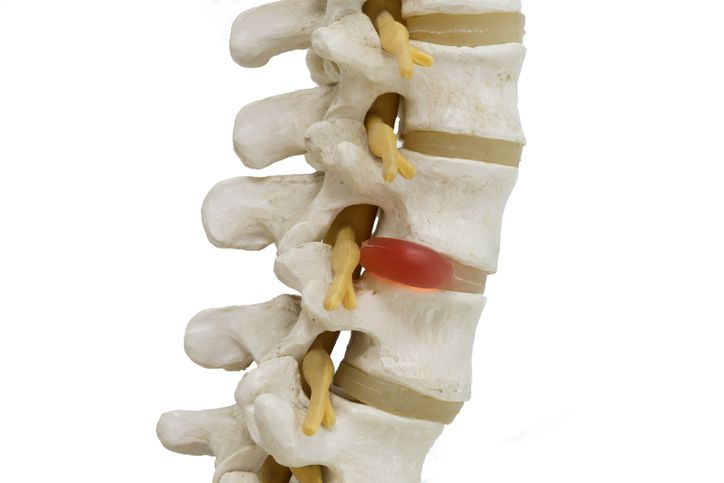

8. A ruptured or herniated disc

Image Credit: undefined undefined/iStock.

9. Sciatica

When a herniated disc presses on the sciatic nerve.